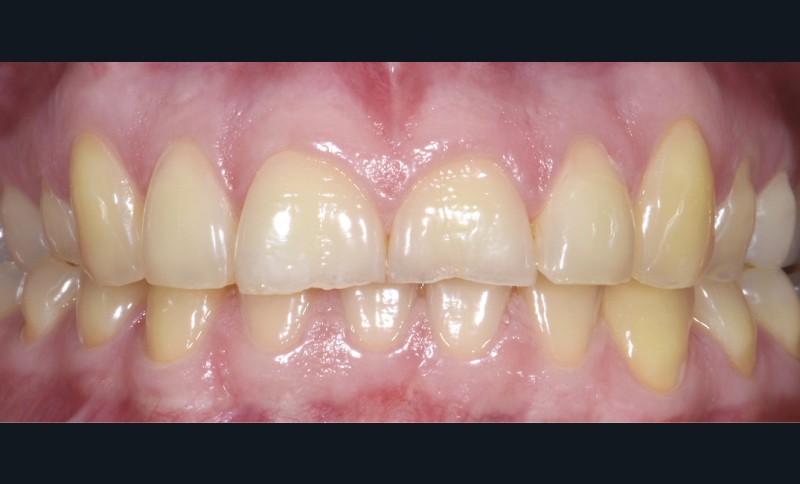

Une patiente âgée de 28 ans se présente en consultation avec une inquiétude au sujet de ses dents postérieures : elle a observé une usure avec un « jaunissement » des faces occlusales et se plaint de sensibilités répétées (fig. 1 à 3).

L’examen général met en évidence un bruxisme nocturne ainsi qu’une consommation peut-être excessive d’agrumes.